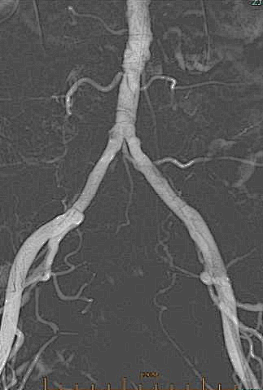

术前CTA:腹主动脉及双下肢动脉粥样硬化改变,左股浅动脉中下段重度狭窄接近闭塞,左股浅动脉下段、腘动脉、膝下分支多处钙化病变。

右侧股动脉翻山入路,经鞘管造影显示下肢动脉多发硬化改变。

左侧股浅动脉中下段局部重度钙化狭窄闭塞,左股浅动脉下段,腘动脉局部中度钙化狭窄。

股浅动脉

腘动脉